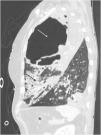

A 63-year-old woman arrived to the Emergency department with cyanosis, severe hypoxia and septic shock. We decided to orotracheal intubation and ICU admission. In the first hours in-ICU, she evolved with worsening of shock, severe refractory hypoxemia, and hypercapnia, without response to prone position, for which she decided to implement support with V-V ECMO, and allow-us to perform a lung CT Scan (Fig. 1) and a bronchoalveolar lavage. Among findings a voluminous abscess communicating with the distal airway indicative of bronchopleural fistula (Fig. 2). In the respiratory cultures, were isolated: Haemophilus influenzae, and Parvomonas micra. Based on these results, we optimized antibiotic therapy. In the following days, envolved with notable improvement, decrease in Noradrenaline until withdrawal. Progressive reduce V-V ECMO parameters until weaning at 12th day. A tracheostomy was performed to wean her from mechanical ventilation. The patient was finally discharged to ward.